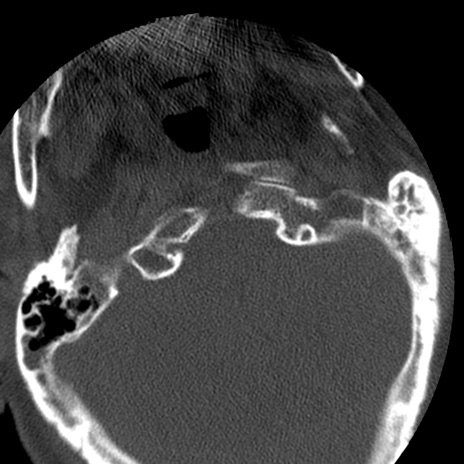

症例50 頚椎CT(横断像)

【症例】60歳代女性

【主訴】後頭部〜右後頸部にかけての痛み

【現病歴】本日飲食店でコーヒーを飲んでいたところ、突然後頭部〜右後頸部にかけて痛みが出現し、右上肢の感覚障害を伴ったため救急要請。

【身体所見】脳神経学的に明らかな異常所見を認めず。右上肢に軽度の感覚障害あり。

異常所見と診断は?

頚椎CT